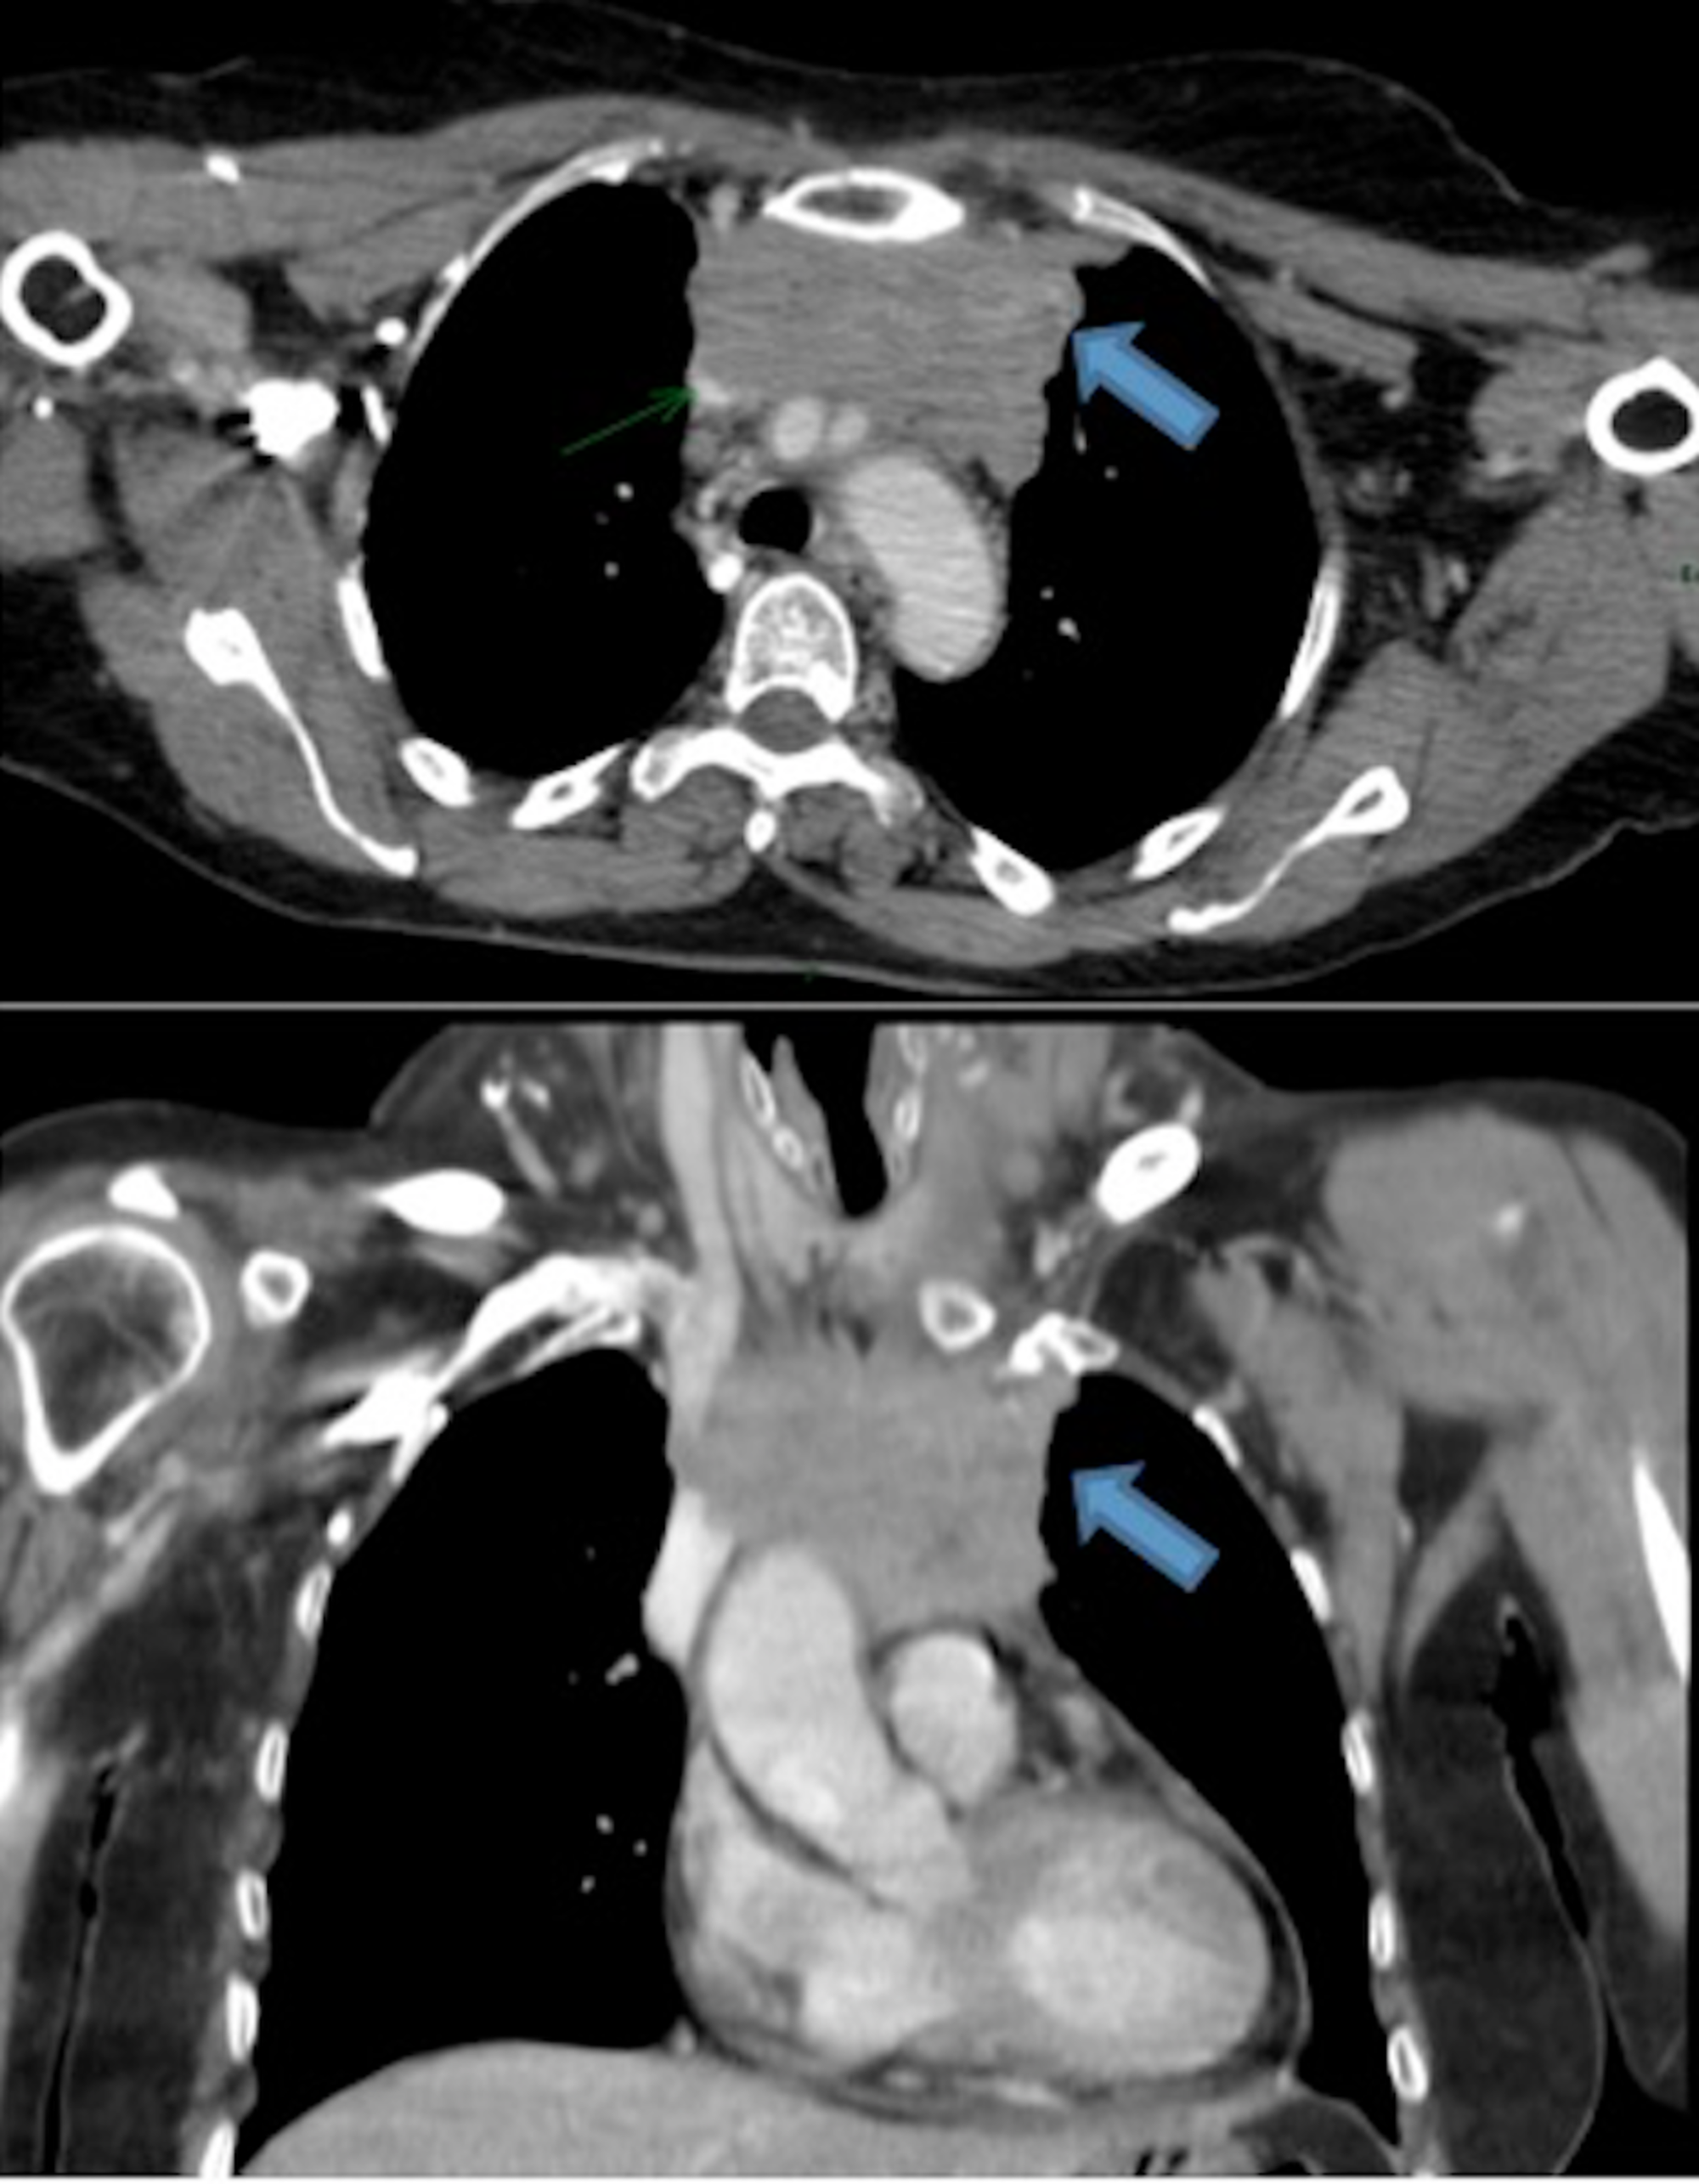

From www.cureus.com

Cureus Metastatic Thymic Carcinoma with Long Survival After Treatment Thymus Cancer Prognosis Tests that examine the thymus are used. A prognosis is the doctor’s best estimate of how cancer will affect. As a rule, the lower the number,. If you have thymus cancer, you may have questions about your prognosis. Survival rates are a way for doctors to discuss the prognosis (outlook) for patients, based on the stage of the cancer or. Thymus Cancer Prognosis.

Metastatic Thymic Carcinoma with Long Survival After Treatment with Thymus Cancer Prognosis The lower the number, the less the cancer has spread. As a rule, the lower the number,. Your cancer can be stage 1, 2, 3, or 4. If thymus cancer has spread to distant parts of the body, such as the heart or the. Survival rates are a way for doctors to discuss the prognosis (outlook) for patients, based on. Thymus Cancer Prognosis.